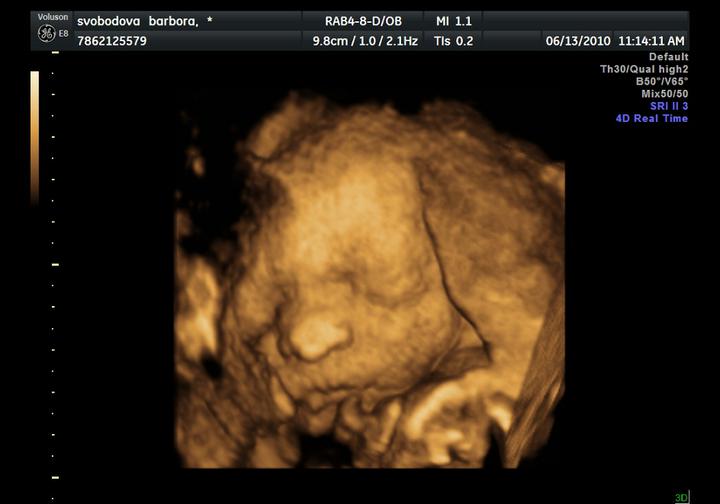

zítra jdeme na 3 D, už se nemůžem dočkat až broučka uvidíme

dneska jsme byli na velkém UZ, Adámek potvrzen a máme 414 g a asi 20 cm, odpovídáme 21+4, krásně rosteme 🙂